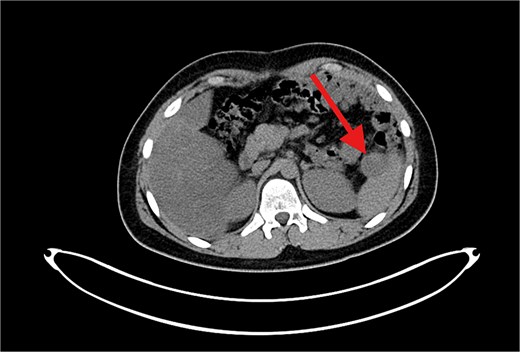

The patient underwent left lateral hepatectomy and cholecystectomy following diagnosis. Histopathology confirmed undifferentiated embryonal sarcoma (UES) of the liver with a 1 mm clear margin (Fig. 1); immunohistochemistry supported the diagnosis. The gallbladder showed chronic cholecystitis, and the lymph nodes were tumor-free. Postoperative imaging after two months revealed a recurrent mass near the stomach (Fig. 2), confirmed as recurrent UES by biopsy. Re-excision showed extensive necrosis and peritoneal infiltration. Positron emission tomography – computed tomography (PET-CT) later identified peritoneal and mesenteric metastases (Fig. 3). Follow-up PET-CT also revealed multiple small hypermetabolic hepatic nodules in addition to peritoneal and mesenteric lesions, indicating intrahepatic disease recurrence. Six cycles of chemotherapy resulted in near-complete resolution of metabolic lesions, with minimal residual activity. Follow-up imaging showed near-complete resolution of hepatic nodules, with only one residual, non-suspicious tiny nodule. After additional chemotherapy and targeted therapy cycles, PET-CT revealed new focal hypermetabolic activity near the splenic flexure, anterior to the spleen, raising concern for recurrence (Fig. 4). The patient underwent omentectomy and splenectomy. Histopathology confirmed metastatic UES in a 2.5 cm splenic lesion with hemorrhage and necrosis, and a 0.4 cm omental nodule, both completely excised. A total of 15 chemotherapy cycles were completed. Post-treatment imaging showed a mixed-density lesion in the splenic bed with FDG uptake, possibly post-surgical, and a new hypermetabolic mesenteric nodule (Fig. 5). Magnetic resonance imaging showed a cystic post-surgical collection without enhancing lesions. Subsequent imaging revealed regression of the splenic bed lesion and resolution of the mesenteric nodule; however, a new hypermetabolic mesenteric density emerged (Fig. 6). The lesion was placed under active surveillance, with additional chemotherapy administered and repeat imaging scheduled to assess response. Bilateral axillary lymph nodes showed reactive hypermetabolism. The patient, having undergone hepatectomy, splenectomy, and multimodal therapy, remains under close surveillance with encouraging treatment response.

Contrast-enhanced axial CT image showing a large, heterogeneously enhancing soft tissue mass measuring ⁓11 × 5.5 × 8.3 cm in the left subphrenic region, abutting, and indenting the greater curvature of the stomach. The lesion demonstrates internal cystic and necrotic components, consistent with a recurrent undifferentiated embryonal sarcoma.